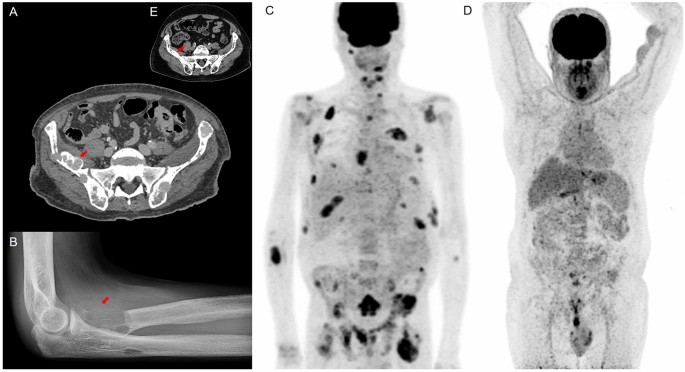

Brown Tumor Of Hyperparathyroidism Springerlink